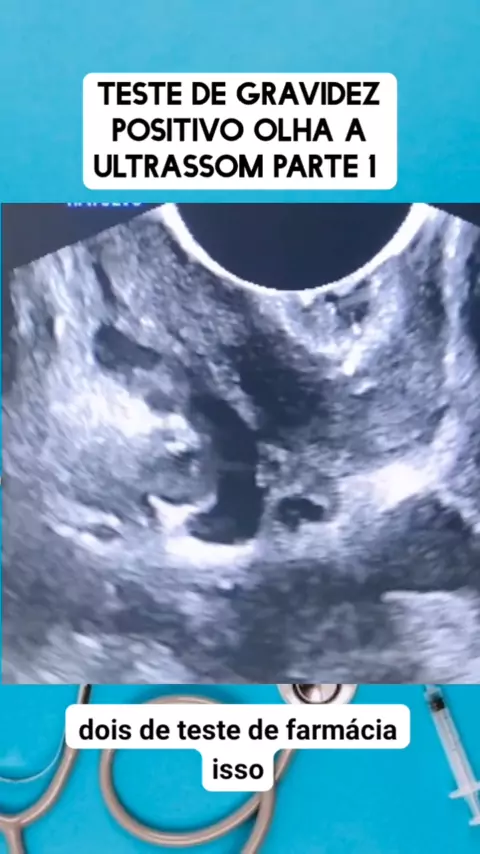

teste deu positivo olha a ultrassom parte 1 #medico #medicina #Saúde #viraliza